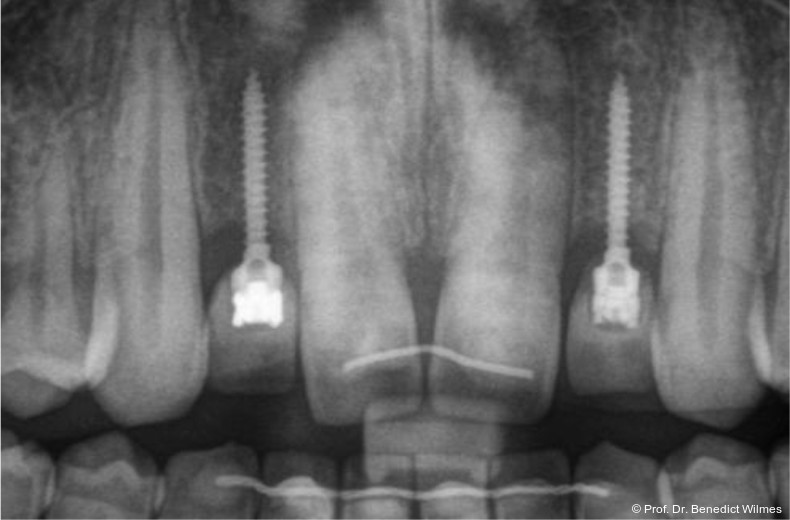

Ein 14-jähriger Patient wurde bei Aplasie der beiden oberen seitlichen Schneidezähne mit dem Ziel der beidseitigen Lückenöffnung kieferorthopädisch therapiert (Abb. 1a+b). Zum Ende der kieferorthopädischen Behandlung wurden zwei Miniimplantate in Regio 2er als temporärer Zahnersatz inseriert (Benefit System, PSM, 2 x 13 mm, Abb. 2a+b). Nach Abdrucknahme wurden Kronen auf den Peek-Abutments modelliert und diese mit Kunststoff auf die Abutments geklebt (Abb. 3a–d). In den Abbildungen 3 und 4 sind die klinischen und röntgenologischen Nachkontrollen innerhalb der nächsten achteinhalb Jahre dokumentiert. Man erkennt einen sowohl in der Höhe als auch in bukkopalatinalen Breite verbleibenden gesunden Knochen ohne Anzeichen einer Atrophie. Im Alter von 23 Jahren wurden die definitiven Implantate ohne die Notwendigkeit einer Augmentation eingesetzt (Abb. 5) und nach Einheilung prothetisch versorgt (Abb. 6a–e und Abb. 7a–c).